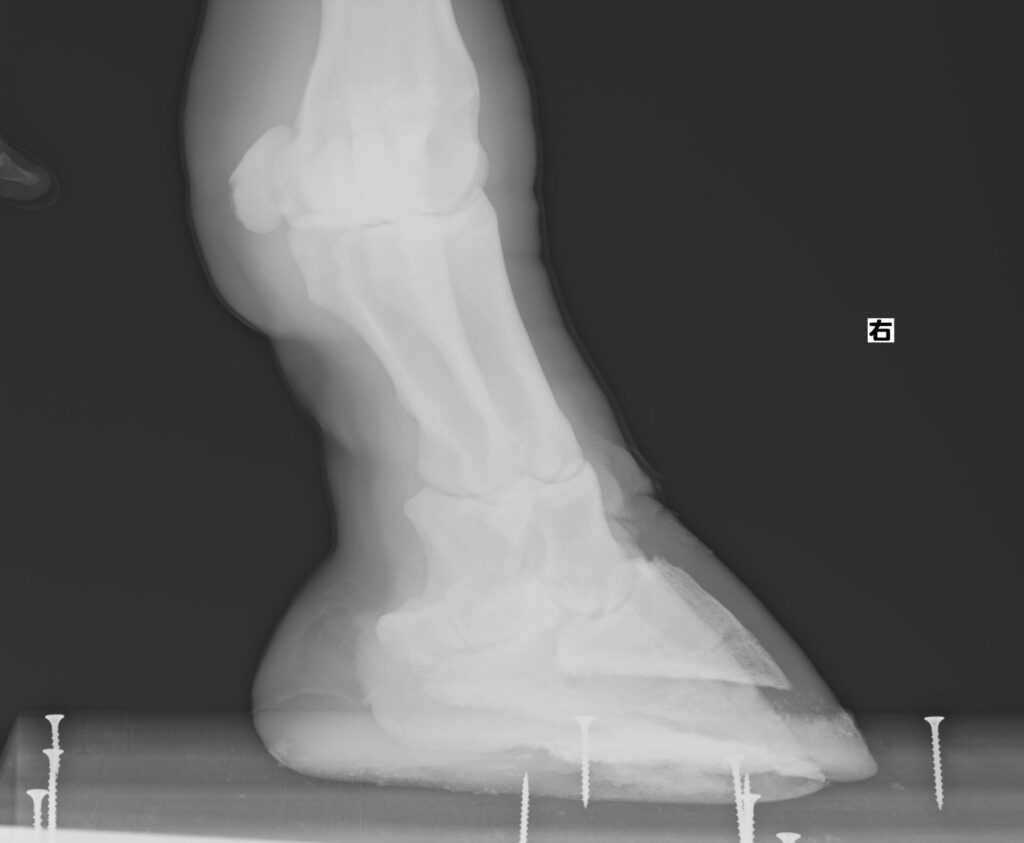

また外見だけではわからないこともあるため、肢のレントゲン撮影にも取り組み始めました。撮影の間じっとしていてもらわなければならないので練習して本番に挑んだところ

撮れました!!

獣医さんいわく今のところ異常なしとのことでホッとしました。

定期的に撮影して骨に異常がないか確認していきたいと考えています。